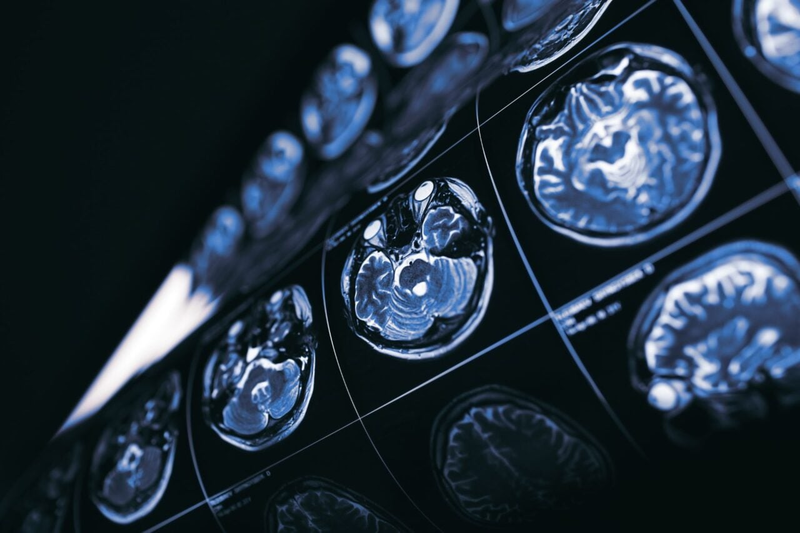

Scientists have found a possible explanation for why cancer patients are less likely to develop Alzheimer's.

Scientists have found a possible explanation for why cancer patients are less likely to develop Alzheimer's.